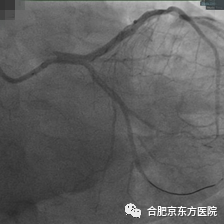

随后的冠脉造影检查证实了医生的判断——耿先生心脏里一根重要血管已经严重堵塞,必须马上手术打通血管。时间就是心肌,心内科胸痛急救医疗团队立即到岗,在孙洪伟主任带领下通过 DSA 介入治疗开通堵塞的心血管。术中 应用药物球囊替代支架植入,通过「介入无植入」的技术手段开通闭塞血管,解除心梗危机。